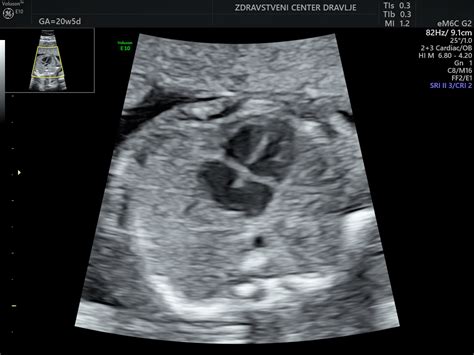

Diagnostika prazne gestacijske vrečke temelji predvsem na ultrazvočnih pregledih. Zgodnji ultrazvok, običajno med 6. in 9. tednom nosečnosti, je ključen. Če je gestacijska vrečka večja od določene velikosti (približno 22-25 mm v premeru) in v njej ni videti zarodka ali srčnega utripa, je diagnoza zelo verjetna.

V primerih, ko je diagnoza negotova ali se zgodnji znaki nosečnosti pojavijo zelo zgodaj, lahko ginekolog predlaga ponovni ultrazvočni pregled čez en do dva tedna. V tem času se lahko pokažejo spremembe, ki potrdijo ali ovržejo diagnozo:

- Nadaljnja rast gestacijske vrečke brez zarodka: Če vrečka še naprej raste, a zarodka še vedno ni, se verjetnost uspešne nosečnosti zmanjšuje.

- Zmanjševanje velikosti gestacijske vrečke: To je znak, da nosečnost propada.

- Pojav srčnega utripa: Če se v tem času pojavi srčni utrip, je to dober znak in nosečnost se lahko nadaljuje.

V primerih, ko se ugotovijo dve gestacijski vrečki, od katerih je ena prazna, obstaja možnost, da se nosečnost nadaljuje. Prazna vrečka se lahko sama izloči ali pa jo zdrava nosečnost potisne ob steno maternice, kjer počasi izgine. Če pa se v vrečki, ki naj bi vsebovala plod, srčni utrip ne pojavi v določenem času (običajno 1-2 tedna), je nosečnost verjetno ne bo uspela.